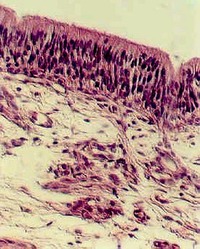

The luman is lined with ciliated Pseudostratified columnar epithelium with Goblet cells. The Epithelium is supported by a basement membrane which rests on a slightly condensed layer of connective tissue. The photograph to the left is a semithin section of trachea embedded in plastic.

The epithelium continues the pseudostratified characteristics seen in the Olfactory epithelium. It is also ciliated and contains goblet cells.

The connective tissue under the epithelium is called the "adventitia". In this connective tissue are numerous seromucous (mixed) glands, as well as blood vessels and nerves. These are called "tracheal glands". Identify the serous and mucous cells in the glands on your section and also on this photograph (to the left). Serous glands contain proteinaceous granules and are therefore stained light purple. The mucin in the mucous glands is washed out. The mucous glands are therefore the lightest staining. What is the function of these glands?